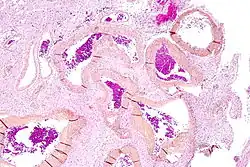

![]() | |

| Micrograph of an arteriovenous malformation in the brain. HPS stain. | |